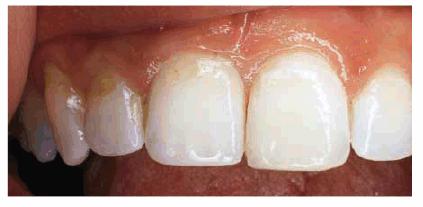

. Amount of tooth destruction present. Generally, small chips or

fractures are easily restored with direct bonded composite resin (Figur 323s1823d es 18-2A, and 18-2B). The esthetic result is excellent

and provides the patient with an economic, one-appointment solution without any

anesthesia.9,10 However, if the patient continues to chip or

Figur 323s1823d e 18-2A: This teenager chipped her maxillary front teeth.

Figur 323s1823d e 18-2B: The left central incisor was bonded with composite resin.